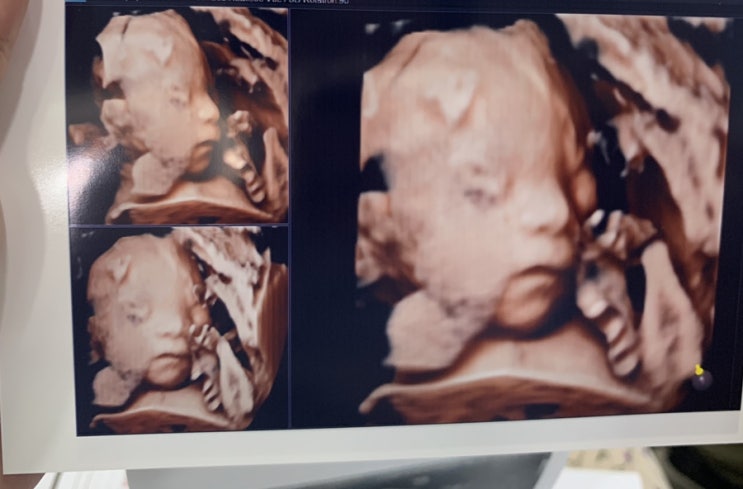

임신 중기 후반 28주차 29주차 증상 및 일상

증상 28주 중반쯤, 처음으로 배가 너무 무거워서 잠들지 못했다. 보통 왼쪽으로 눕는게 편하다고 하는데 나...

임신 26주차 증상 임당검사 정밀초음파

임신 26주 증상 배 크기가 쑥쑥 올라가는 중. 출근했더니 우리팀원분들 몇 분이서 순식간에 배가 불러 오는...